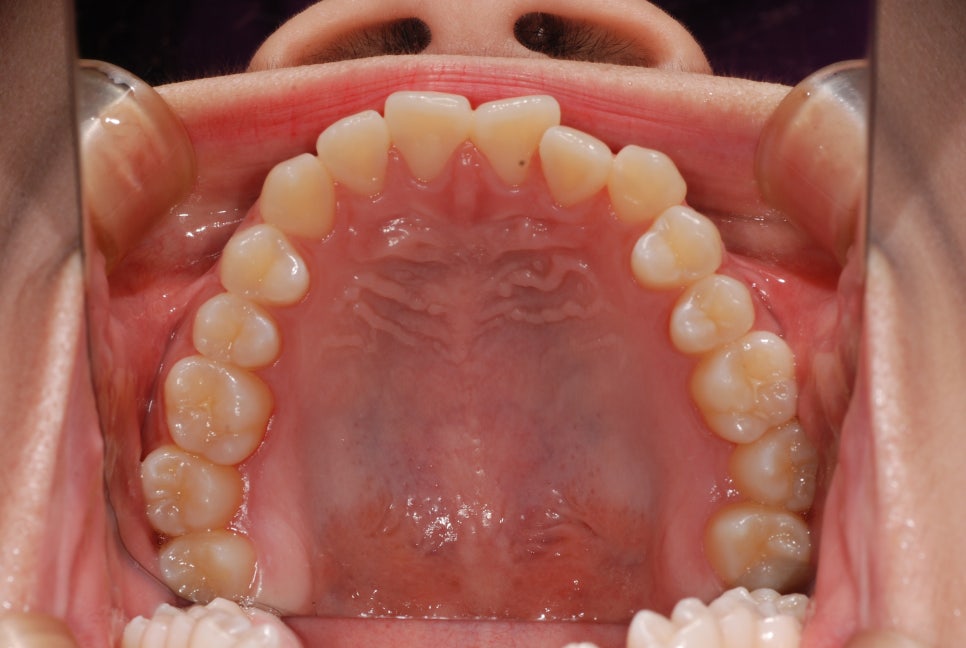

또한 작은 위턱으로 인해

위 앞니의 위치 자체가

아래 앞니 보다 뒤에 위치하게 되는데,

이를 보상하기 위해 앞니들이

순측경사(앞으로 뻐드러짐)되어 있습니다.

입술(순측)으로 경사를 이루던 앞니를

설측(혀)가 있는 쪽으로 기울어지게 유도하고,

이와 더불어 씹는면 쪽으로 정출되도록

움직임을 만들어냅니다.